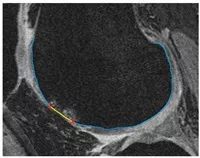

Bone Volume Fraction (BVF) Description:

We have a customized semi-automatic software to measure trabecular bone volume (BV/TV)

Around 8 min/knee MRI.

Intra-tester (ICC [3,1] = 0.99).

Bone volume

Driban JB, Barbe MF, Amin M, Kalariya NS, Zhang M, Lo GH, Tassinari AM, Harper D, Price LL, Eaton CB, Schneider E, McAlindon TE. Validation of quantitative magnetic resonance imaging-based apparent bone volume fraction in peri-articular tibial bone of cadaveric knees. BMC Musculoskelet Disord. 2014;15:143.